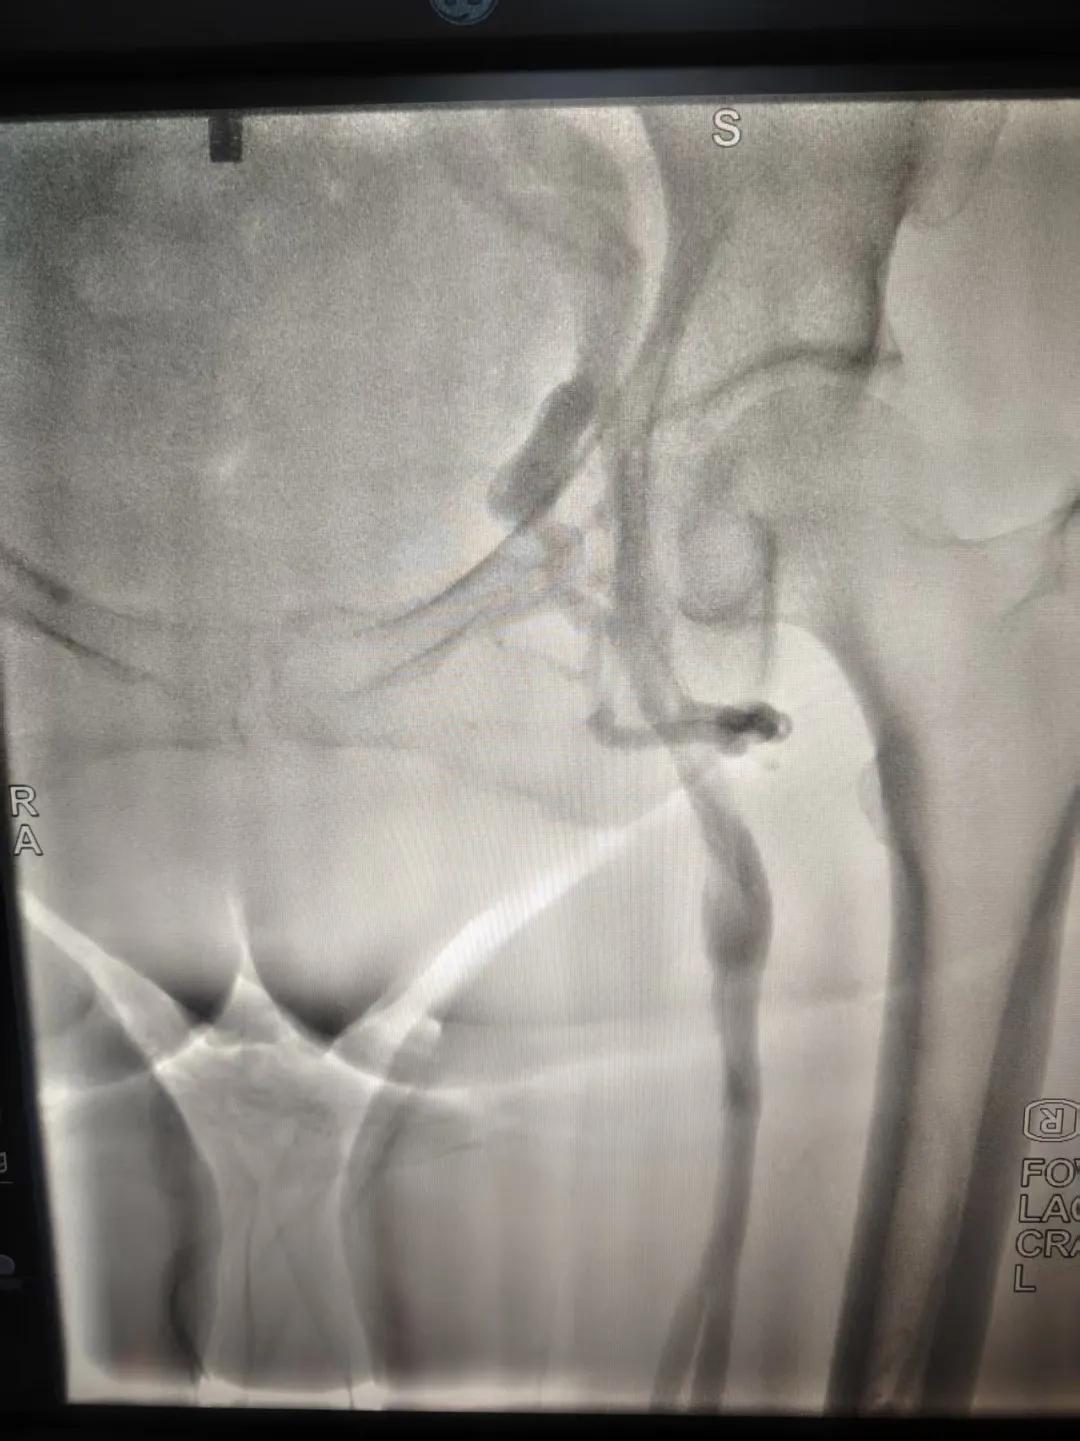

該患者,中年女性,左下肢反復(fù)腫脹、疼痛多年就醫(yī),未明病因。門診就診,經(jīng)血管外科副主任周創(chuàng)業(yè)評(píng)估病情后,為該患者門診行下肢靜脈造影,造影結(jié)果示:左髂靜脈周圍側(cè)枝形成,左髂靜脈壓迫綜合癥。明確診斷后將擇期介入手術(shù)治療。

下肢靜脈造影是診斷下肢靜脈病變(如深靜脈血栓、靜脈曲張、靜脈功能不全等)的“金標(biāo)準(zhǔn)”。靜脈造影可直觀顯示受壓部位、狹窄程度及側(cè)支循環(huán)形成情況,明確診斷與定位,指導(dǎo)治療決策,以及介入治療規(guī)劃,血栓評(píng)估,在復(fù)雜病例或介入治療中造影具有優(yōu)勢(shì)。